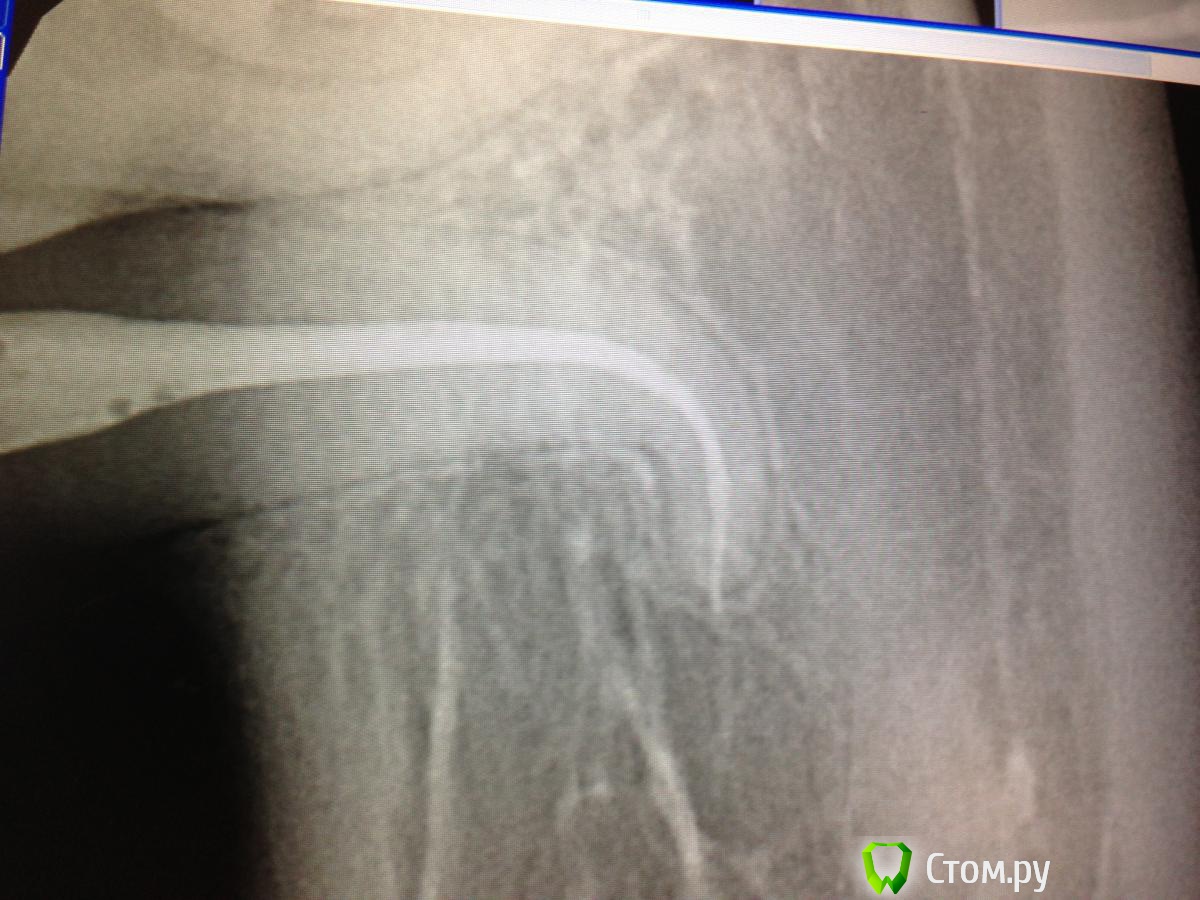

SSTi Опубликовано 5 мая, 2014 Автор Поделиться Опубликовано 5 мая, 2014 38. Пульпитный. Медиальные сходятся. Забавная кривулька вышла. ))))Латералка 2 Ссылка на комментарий

Shaid Опубликовано 5 мая, 2014 Поделиться Опубликовано 5 мая, 2014 В дистальном без петенси? Такое ощущение, что последние 2 мм остались недопакованными и апекс "зияет". Ссылка на комментарий

SSTi Опубликовано 5 мая, 2014 Автор Поделиться Опубликовано 5 мая, 2014 Да вот сижу смотрю сейчас и тоже так кажется. Хотя все по локатору ок было. И упор четкий. 16 мм рабочая в дистальном. 16.5 уже пищал , что вышел за апекс. Ссылка на комментарий

SSTi Опубликовано 20 мая, 2014 Автор Поделиться Опубликовано 20 мая, 2014 пульпитный 35. с сюрпризом в виде кривульки. Доступ дистально. коффер, обработка ручными к-файлами, машинные протейперы( до ф2), профайлы. Много гипохлорита, уз.Все время было чувство, что сломаю файл за изгибом, или нарежу ступень... но пронесло)) боялся, что не дойду до апекса(апекслокатор не начинал пока даже попискивать), потом дошел, отступил 0,5, сделал упор и вот тебе результат- вышел на 0,5.... 8 Ссылка на комментарий

SSTi Опубликовано 20 мая, 2014 Автор Поделиться Опубликовано 20 мая, 2014 кстати он находится на месте 7ки, а 36 на месте 38. между 35 и 34 сантиметра 1,5-2.3,7 и 3,8 нет Ссылка на комментарий

SSTi Опубликовано 20 мая, 2014 Автор Поделиться Опубликовано 20 мая, 2014 (изменено) Спасибо)Я никогда не забуду хруст протейперов в этой пятерке и мысли о том, как доставать если вдруг ...))) что-то везет в последнее время на кривули такие. Кстати рд здесь-25.5 мм. Напрягает, когда эндонаконечник вплотную к зубу и ты не видишь файла..... Изменено 20 мая, 2014 пользователем SSTi Ссылка на комментарий